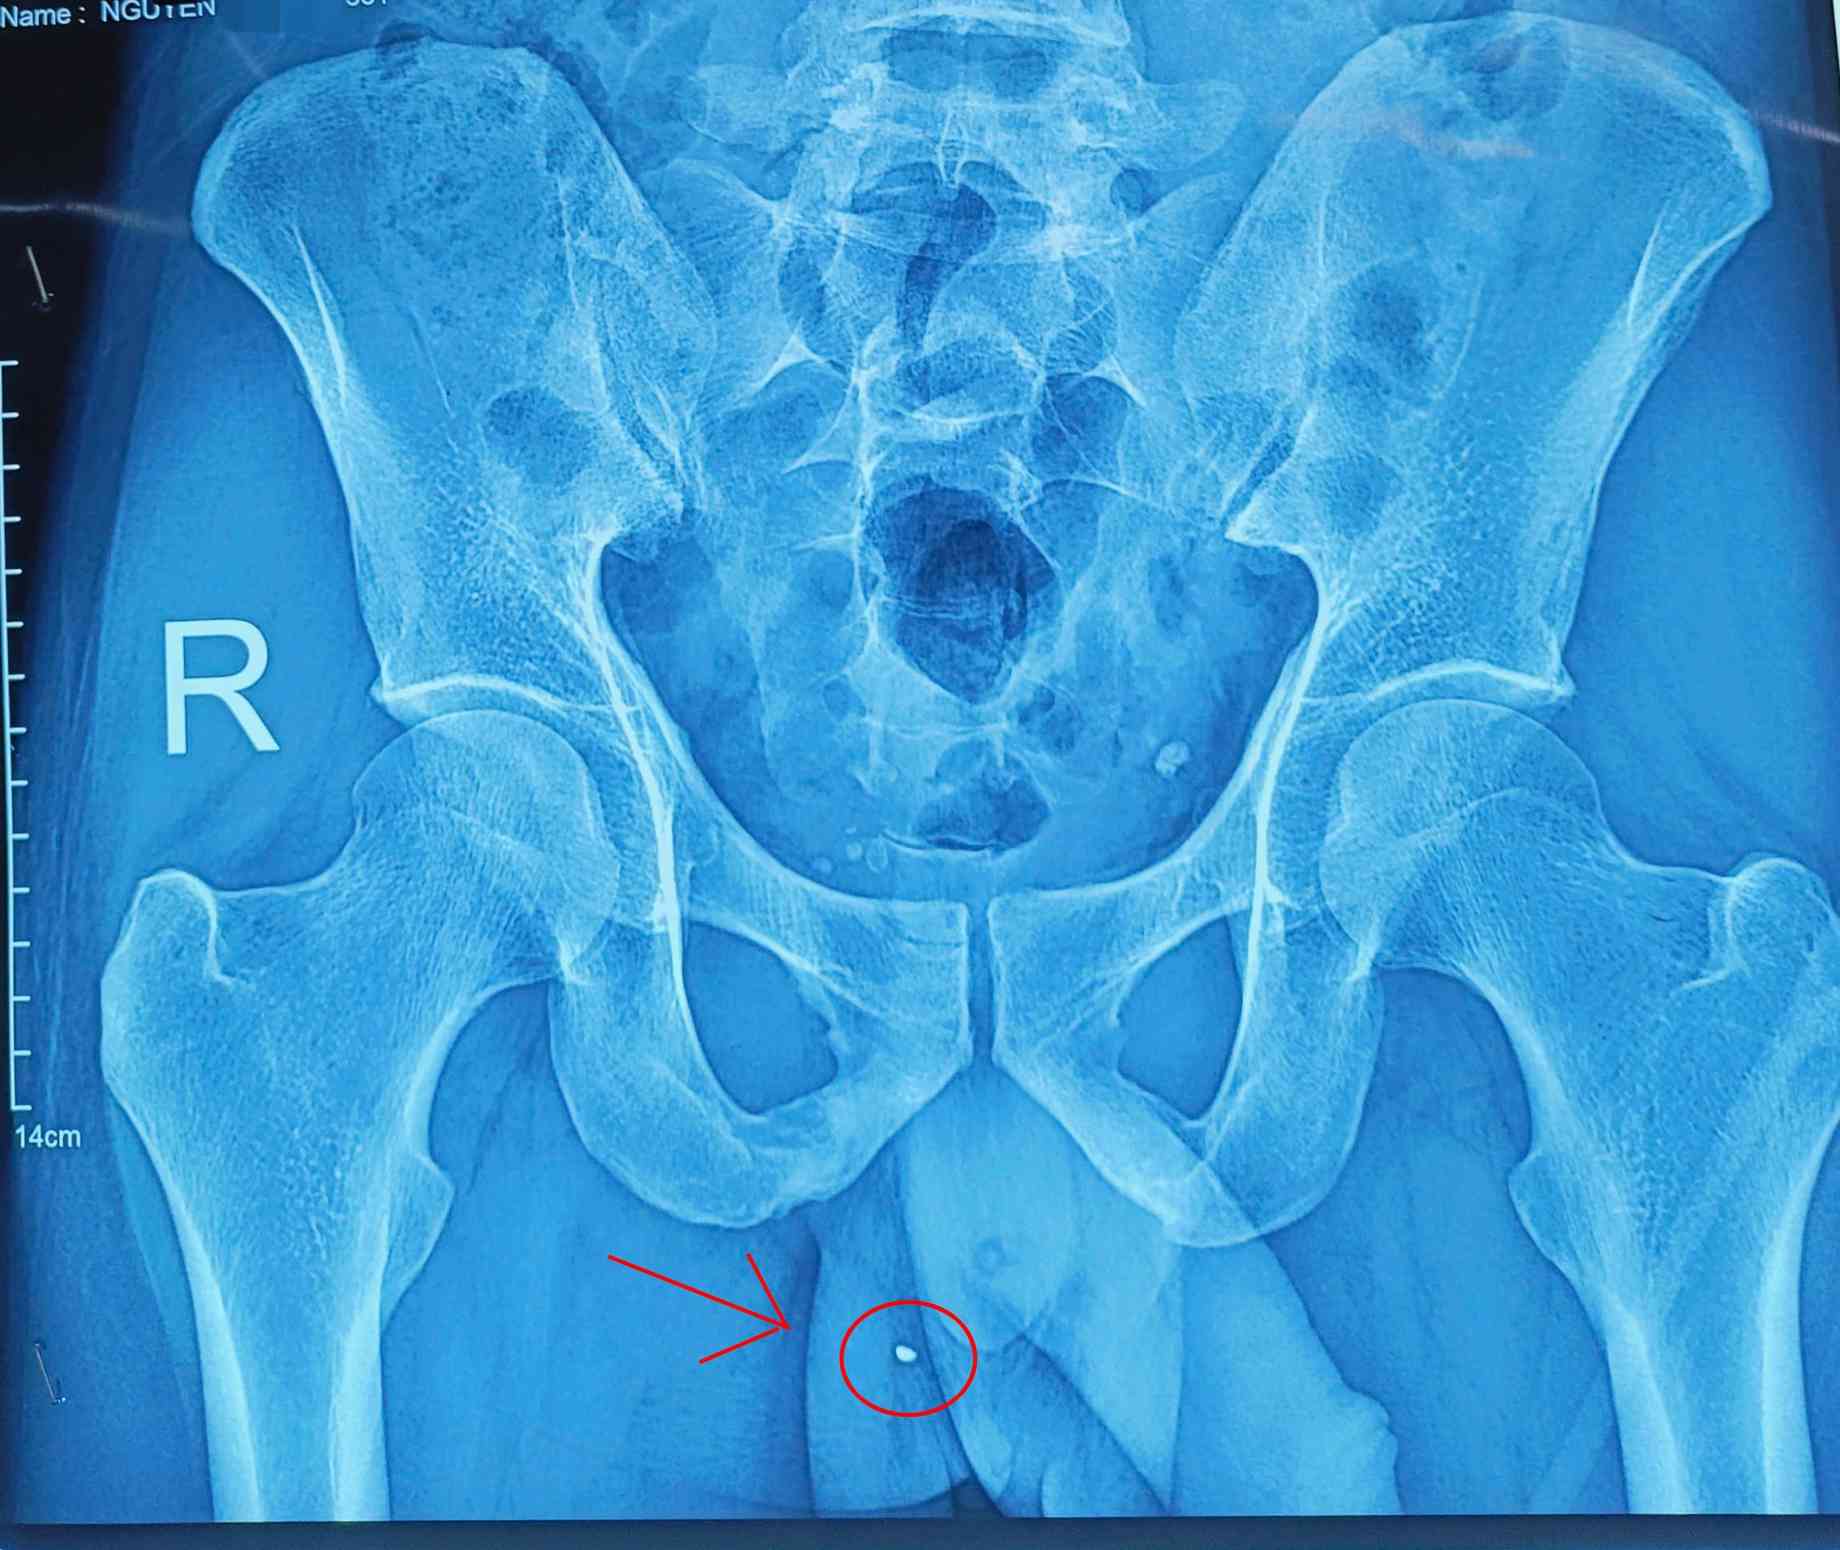

Pediatrico hospitalizado en un estado de vomitos mucho, causas desconocidas. Inicialmente, el ultrasonido abdominal no se registro anormalmente, pero debido a los vomitos prolongados, el medico receto una radiografia. Los resultados mostraron que la imagen sospechosa tenia objetos gastrointestinales. Sin embargo, no se detectan tanto gastroscopia como colorrectal.

Enfrentando signos poco claros, los medicos han ampliado la direccion de diagnostico y los objetos extraños sospechosos pueden estar en el tracto genital. Despues de una prueba exhaustiva, descubrieron el objeto que se encontraba en la vagina, una posicion poco comun, especialmente en niños pequeños.